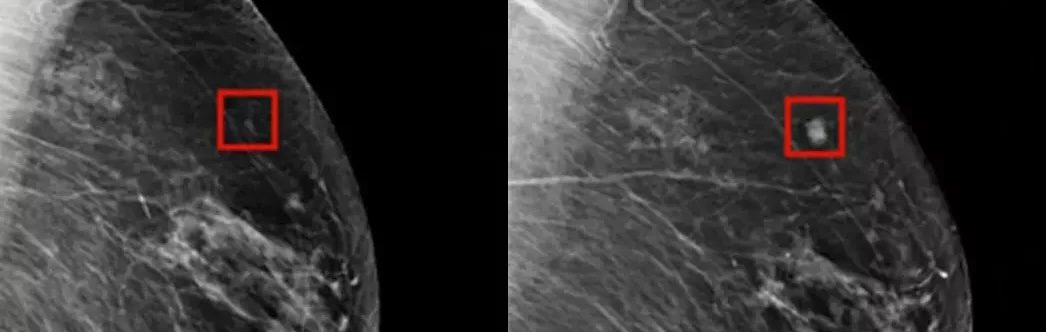

Nová technológia používajúca AI však umožňuje detekovať rakovinu prsníka oveľa skôr, než by to dokázali lekári. Podľa nedávneho článku v CNN, AI program bol schopný úspešne zistiť rakovinu prsníka u ženy až štyri roky predtým, než sa vyvinula a bola diagnostikovaná tradičnými metódami.

Tak ako to funguje? AI sa používa na skríning rakoviny prsníka s cieľom identifikovať potenciálne problémy ešte dlho predtým, než sa vyvinú do niečoho škodlivého. Technológia funguje tak, že strojové učenie (machine learning) umožňuje AI vyhodnocovať obrazy a porovnávať ich s tými, ktoré už boli zaznamenané v stroji, aby identifikovali nezrovnalosti a prípadné rizikové oblasti.

Podľa Dr. Larryho Nortona z Lauder Breast Center, AI pomáha radiológom lepšie pozrieť sa na obrazy a identifikovať oblasti, ktoré by si možno inak nevšimli. Výhoda tejto technológie spočíva v tom, že dokáže identifikovať potenciálny rizikový faktor u pacienta ešte predtým, než sa vyvinie rakovina.